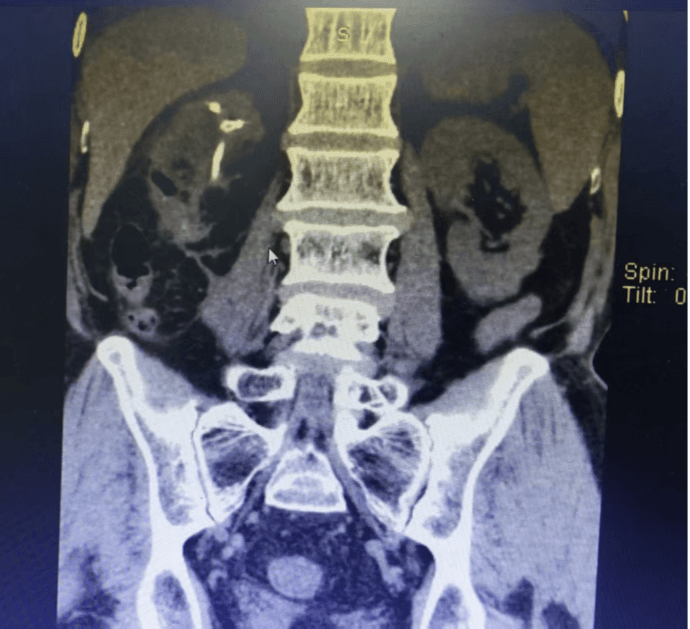

术后复查CT

术中,麻醉科精准调控,手术团队先在局部麻醉下为杨爷爷进行经皮右肾穿刺造瘘、结石碎石取石、输尿管支架置入术,手术过程中出血极少,局部麻醉+微创的优势能够较好地建立耐受,解除杨爷爷右肾结石引起的尿路梗阻,尿路感染得到很好控制后。再二期全麻下行“经皮右肾+经尿道输尿管软镜双镜联合碎石取石”。术后,杨爷爷恢复良好,胸腔积液吸收,低蛋白血症、贫血也得到纠正,尿路梗阻及肾功能得到了很好的恢复。